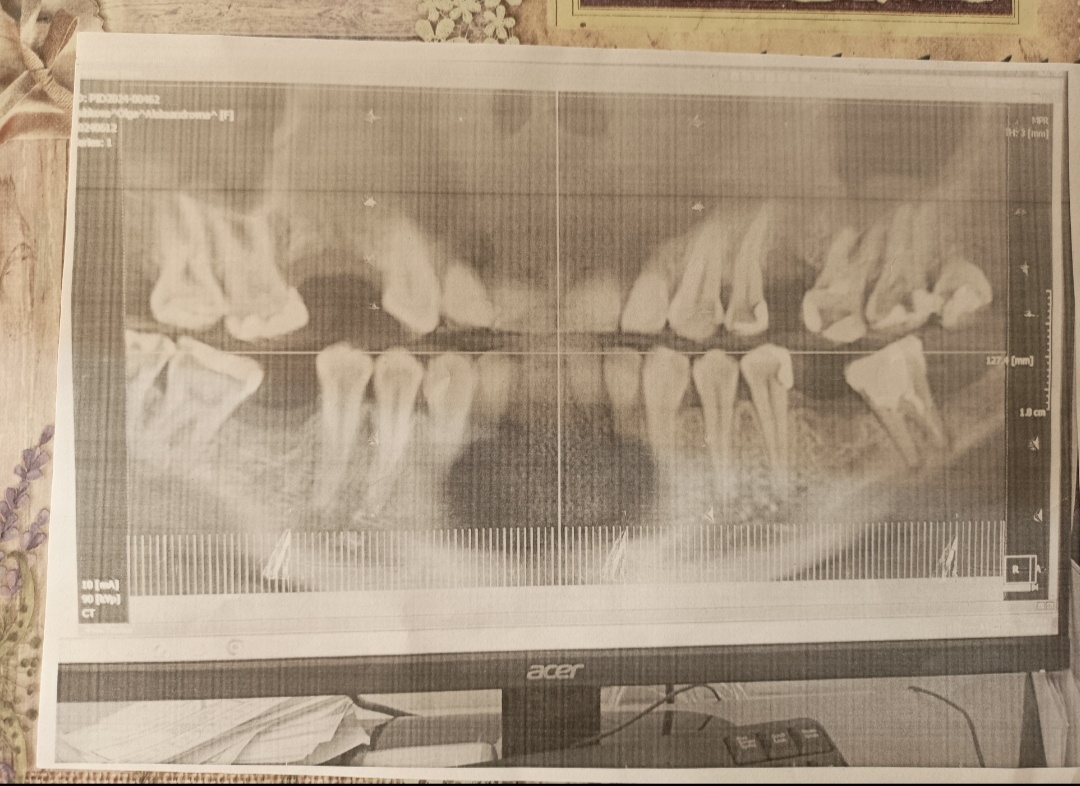

А ещё плюсом скинули вот такое на телефон

В итоге её вердикт был, что судя по кт(который больше нигде кроме как у них не открывается), зубы мне пролечили "плоховато". Ту многострадальную семёрку она бы советовала перелечить. Сказала - в каналах практически нет материала. Верхнюю шестёрку, на которой меняли старую пломбу, тоже советовала бы пролечить канально, хоть она и мёртвая🤔.

В общем и целом до трансплантации с такими зубами она бы меня милостиво допустила). Инфекции вроде как нет. Но в дальнейшем, сказала, скорее всего, придётся перелечивать...